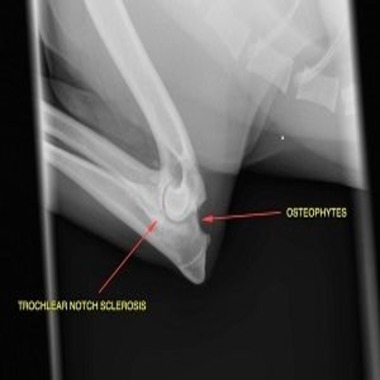

Elbow Dysplasia in Dogs and Medial Coronoid Disease

Learn about Elbow Dysplasia in dogs, what does elbow dysplasia look like in dogs, treatment and diagnosis from our expert Veterinarians.